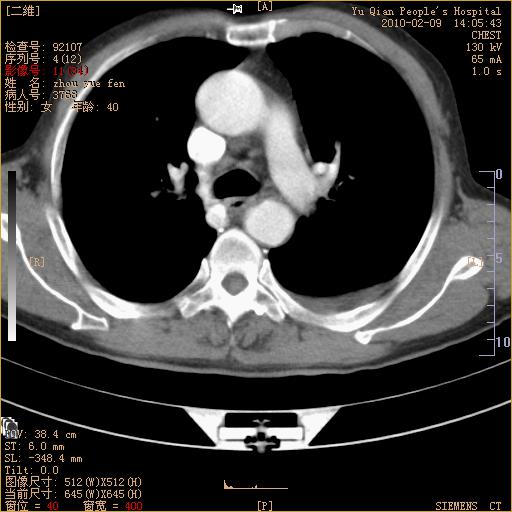

男性,73岁,咳嗽咳血数天,诊为肺ca伴左肺下叶后段阻塞性炎症、肺不张妥否?

右下肺有转移?

左下肺中央型肺癌伴结段形肺不张,左侧胸腔积液,纵隔内见部分增大淋巴结(反应性增生或转移)

左下基底干支气管明显变窄。

左肺下叶基底段支气管狭窄,左肺门增大,左肺下叶团片状病灶。中心型肺癌伴柱塞性炎症可能大,建议支气管镜检查。

左下肺中央型肺癌伴节段性肺不张,左侧胸腔积液,纵隔内见肿大淋巴结

左下基底段支气管变窄。建议进一步纤支镜检查。

1、左肺下叶后基地段肺癌伴阻塞性炎症,左下肺门淋巴结转移。2、左侧胸腔积液。